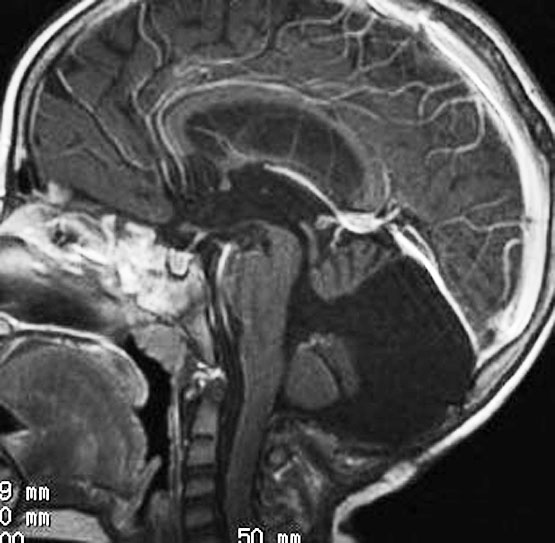

20代女性に偶然発見された視床下部(第3脳室)腫瘍です,T1低信号,T2で高信号,右側のガドリニウム造影では全く増強されません。毛様細胞性星細胞腫と診断できます。眼科での視野検査で視野欠損はありませんでした。生検術もなにもせず経過をみました。

左が初診時,右が5年後のMRI画像です。腫瘍の大きさは全く同じです。このような腫瘍はしばしば経験します。慌てて生検術や開頭手術など計画しないで,画像診断をしっかりすることが大切です。